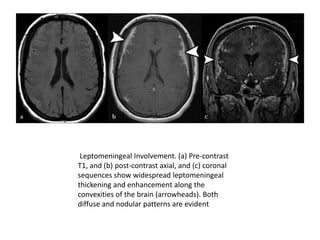

Leptomeningeal Involvement. (a) Pre-contrast

T1, and (b) post-contrast axial, and (c) coronal

sequences show widespread leptomeningeal

thickening and enhancement along the

convexities of the brain (arrowheads). Both

diffuse and nodular patterns are evident